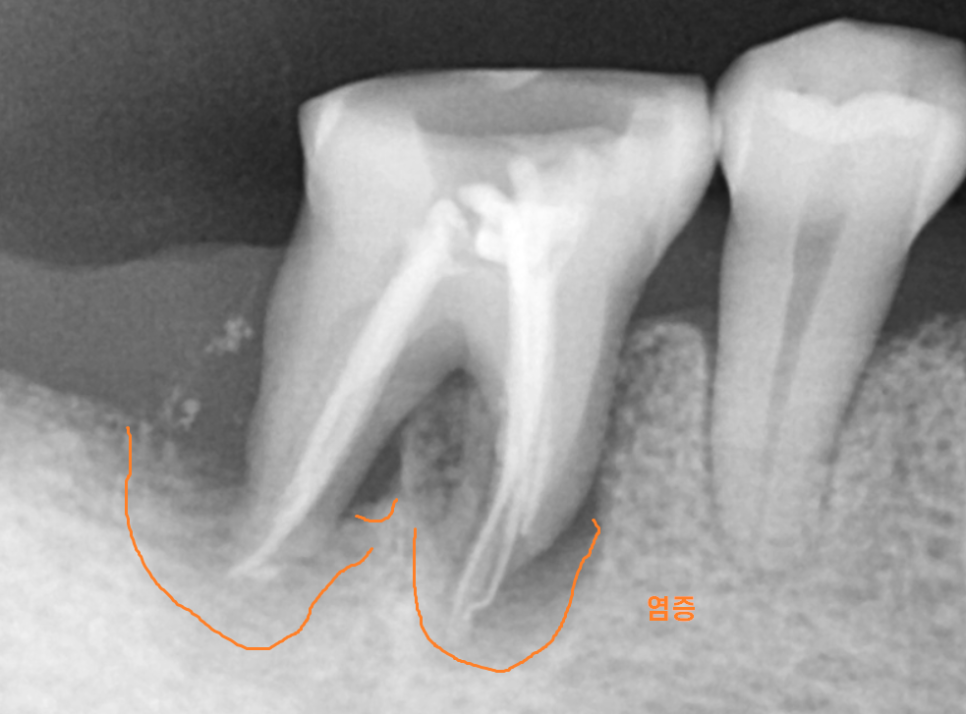

해당 환자분은 뿌리 끝에 염증이 생기셨는데요~

때문에 뼈가 많이 녹아있는 상태였습니다.